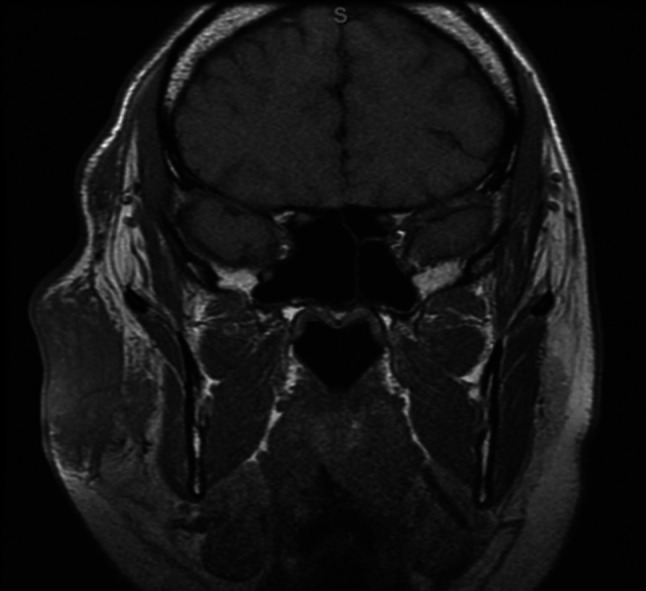

A 39 year-old male presented to the University of Texas Medical Branch Otolaryngology clinic with facial pain and cosmetic deformity caused by a slowly growing right facial mass. The mass first appeared in 2015, but the patient did not seek care until 2017. At that time, a community plastic surgeon performed a surgical resection. The lesion recurred shortly thereafter and the patient was then treated with systemic corticosteroids without improvement. Upon presentation to our clinic, physical exam revealed a large right facial mass extending from the supraorbital rim superiorly to below the angle of the mandible inferiorly without overlying skin change. CT and MRI demonstrated a subcutaneous heterogeneously enhancing mass involving the right parotid as well as infra-temporal and supraorbital soft tissues without extension into the orbit (Figs. 1 and 2). Additionally, multiple pathologic lymph nodes were seen in the region surrounding the right parotid as well as right levels II-IV.

Fig. 1.

MRI orbits without contrast T1 sequence showing large right sided preauricular lymphadenopathy